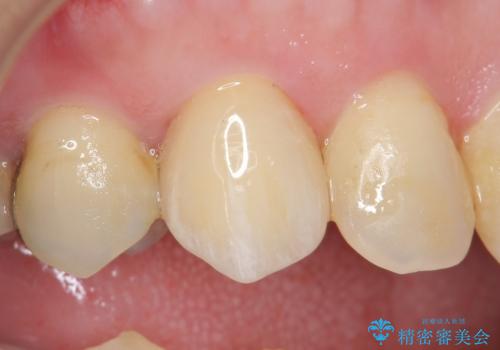

オールセラミッククラウン(スペシャル) 根管治療後の補綴

再根管治療を行い症状が治まったのを確認後、オールセラミッククラウン(スペシャル)による補綴を行いました。

前歯の補綴ではオールセラミッククラウンを希望される患者様が多いですが、オールセラミッククラウンの中でも、エコノミー、スタンダード、スペシャル、エクセレントとランクがあります。

その中でも特に審美性が高いのがスペシャル、エクセレントです。スペシャル、エクセレントは口腔内写真をもとに熟練の技工士が、患者様の口腔内に合わせたオーダーメイドのクラウンを製作致します。